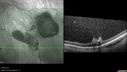

51 year old male with a broken vein in the left eye. His vision is pretty good. He has not noticed any vision change. You asked him to come here for further evaluation in the left eye. VA OD: sc20/63 PH20/25-2 NccJ1 VA OS: sc20/20 Patient had scatter laser to non-perfused retina and never had a vitreous hemorrhage (yet)

Coats' Disease -51 year old asymptomatic male450 views20/20 vision - had laser to non-perfusion because of proliferation.00000